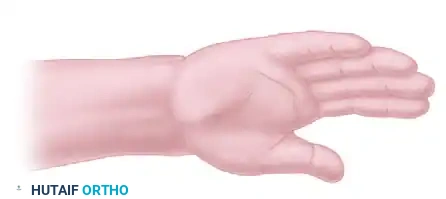

Step 1: Incision and Exposure

Make a curvilinear dorsoulnar skin incision at the wrist level. The incision should be centered over the distal ulna, allowing access to both the dorsal and palmar aspects of the ulnar stump.

Figure 1: The planned curvilinear dorsal skin incision over the distal ulna.

Extend the incision proximally along the distal ulnar shaft.

If additional palmar exposure is required to adequately mobilize the pronator quadratus, a supplementary palmar incision can be utilized, though the procedure can often be completed through a single extensile dorsoulnar approach.

Figure 2: Optional palmar skin incision for extended access to the pronator quadratus.